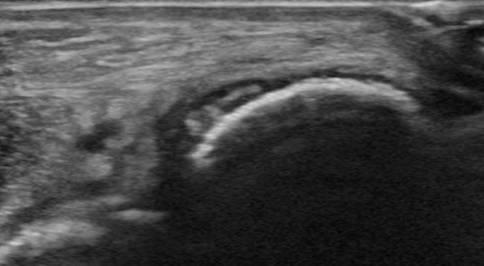

Tụ mủ dưới màng xương

Viêm xương tủy

» Thông tin: Nam giới – 11 tuổi.

» Lâm sàng: Sưng đau cẳng chân.

# Tụ mủ dưới màng xương.